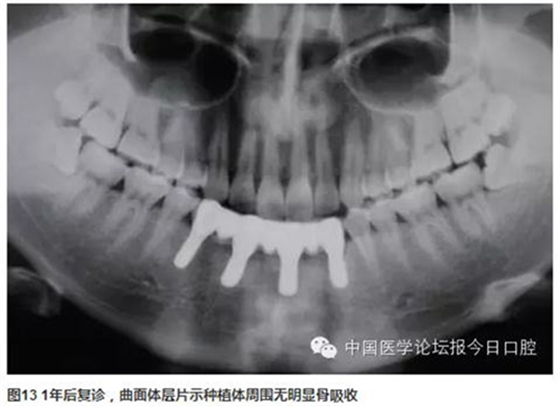

曲面體層片示:種植體基臺與修復體密合性良好。1年后復診,支架無松動、折斷,中央螺絲未見折斷、松動,修復體未見崩瓷。種植體無松動,種植體周圍少量軟垢存,黏膜未見紅腫。種植體周圍探診深度:下頜左側(cè)尖牙(近中2mm、頰側(cè)3mm、遠中4mm、舌側(cè)2mm),下頜左側(cè)中切牙(近中2mm、頰側(cè)2mm、遠中4mm、舌側(cè)2mm),下頜右側(cè)側(cè)切牙(近中2mm、頰側(cè)2mm、遠中3mm、舌側(cè)3mm),下頜右側(cè)第一前磨牙(近中3mm、頰側(cè)2mm、遠中4mm、舌側(cè)3mm)(圖11~圖13)。

下頜多牙連續(xù)缺失,采用CAD/CAM純鈦支架聚合瓷固定修復,修復體精度高,與種植體密合性好,容易實現(xiàn)被動就位,聚合瓷牙齒、牙齦色較易恢復。

患者為外傷導致的下前牙多牙缺失。由于骨吸收導致牙合齦距離增大。前牙區(qū)植入4顆種植體并采用CAD/CAM技術(shù)制作的鈦支架修復體,恢復了患者前牙區(qū)的功能及美學效果,采用牙齦瓷的方案解決了由于牙合齦距離大而導致的可能的牙體過長、與鄰牙及對頜牙不協(xié)調(diào)的問題。術(shù)后1年的影像及臨床資料表明種植體及修復體周圍軟硬組織穩(wěn)定,短期效果滿意。該病例中說明部分為“骨高度不足”,個人覺得更改為“牙合齦距離大”,更為理想。因為無論國內(nèi)外的文獻中,骨高度不足往往指的是頜骨高度對種植體植入的影響;該病例中通過術(shù)前CBCT和術(shù)后的曲面體層片提示下頜前牙區(qū)骨量充足,并不影響種植體的植入。只是由于前牙骨吸收導致牙合齦距離過大,修復體所占的位置較天然牙更大。